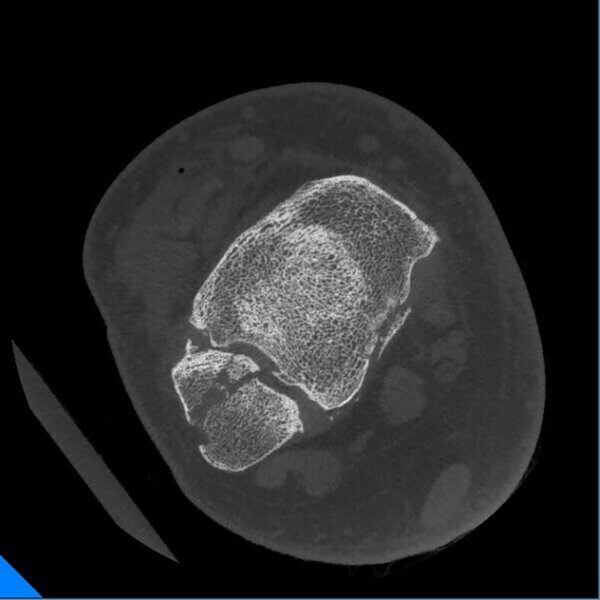

Fractura de escafoides.